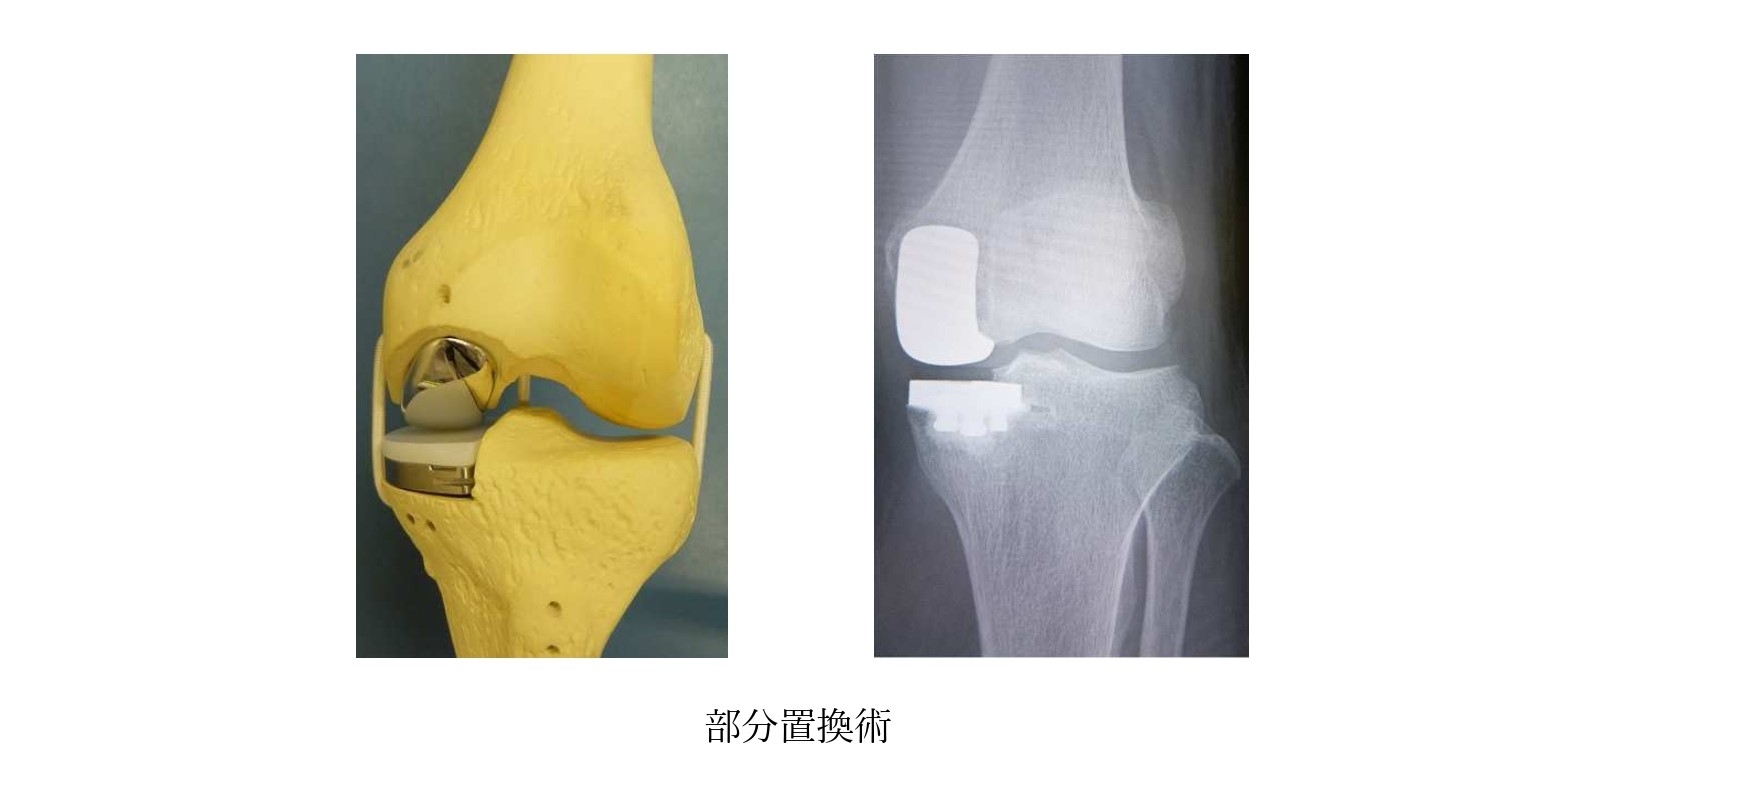

人工膝・股関節手術